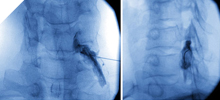

Bilder zu Injektionstherapie und CT-Injektionen

Bildwandlergesteuerte mikrotechnische Injektionstherapie und CT-Injektionen.

Als Mitglieder der Internationalen Gesellschaft für interventionelle Schmerztherapie (ISIS) und der Deutschen Gesellschaft für interventionelle Schmerztherapie (GIS) haben wir die Möglichkeit in unserem Operations- und Eingriffsraum hundertprozentig exakte Injektionen an den betroffenen Ort durchzuführen.

Je nachdem, ob Arthrose die Ursache für die Rückenbeschwerden ist oder ein Bandscheibenvorfall vorliegt, kann man mit einem Kontrastmittel zielgerichtet entsprechende Medikamente an den Ort der Ursache spritzen. Hierbei verwenden wir Mikro-Kanülen. Dieser Injektionsvorgang ist deutlich weniger schmerzhaft als eine vergleichbare Spritze in den Muskel.

Hier besteht ebenfalls wie bei dem uns zur Verfügung stehenden Computertomographen die Möglichkeit, z. B. auch entsprechende Knorpelsubstanzmittel direkt an den Ort des Verschleißes zu injizieren (CT-Injektionen). Darüber hinaus können abschwellende Medikamente oder gentechnologische Produkte an den Ort von Bandscheibenvorfällen appliziert werden, um so das bestehende ödem und daraus folgend den Nerv zu entlasten. Damit können Operationen häufig unnötig werden.